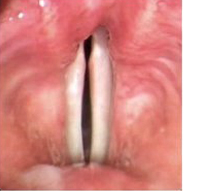

성대구증

성대구증은 성대의 유리연을 따라 평행하게 홈(구; 溝)이 나 있는 질환입니다. 성대점막 고유층의 바깥층으로부터 성대 인대에 걸쳐 겉껍질이 함몰되거나, 위축됨으로써 성대 가장자리가 활처럼 휘어지고, 성문이 완전히 닫히지 않게 됩니다.

발생 원인으로는 선천적 후천적 원인이 다양하게 거론되고 있지만 아직 정설은 없습니다.

증상으로는 과도한 쉰목소리와 고음발성 장애가 뚜렷하며 일반적인 후두내시경으로는 큰 이상을 발견하지 못하는 경우가 많이 있지만, 후두스트로보스코피검사를 통하여 점막파동의 특징을 찾아내 진단할 수 있습니다.

치료는 활처럼 휘어진 성대가 발성시 완전히 닫히지 않는 것을 교정하는 것이 목표가 됩니다. 음성치료는 성대의 부적절한 보상기전을 교정하는 데에는 도움이 되지만 한계가 있습니다.

수술 방법으로 후두미세수술을 이용한 성대내주입술 혹은 갑상성형술1형 등의 성대내전술 또는 성대점막의 직접적인 복구를 위한 성대구 절제 등 여러 가지 방법이 시도되고 있으며 최근에는 PDL 혹은 KTP 등의 레이저를 이용한 수술이 어느 정도의 성과를 거두고 있습니다.